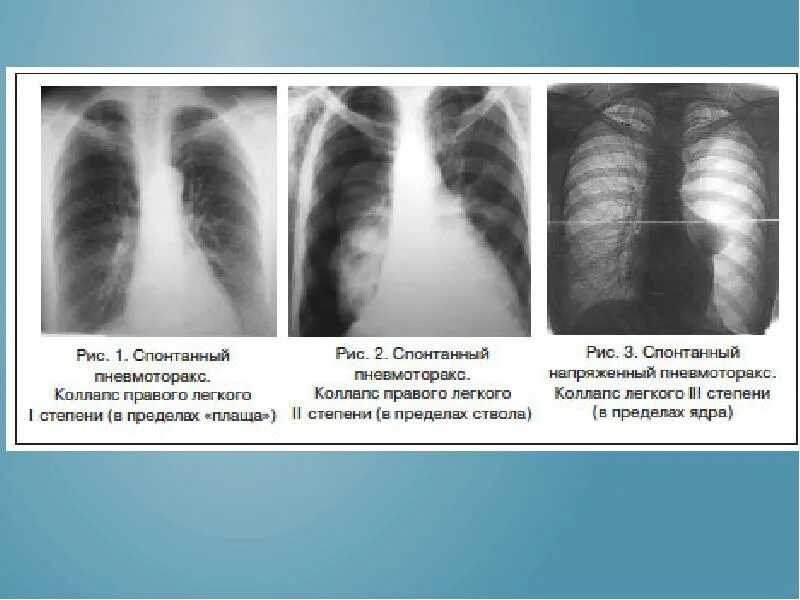

Закончился воздух в легких